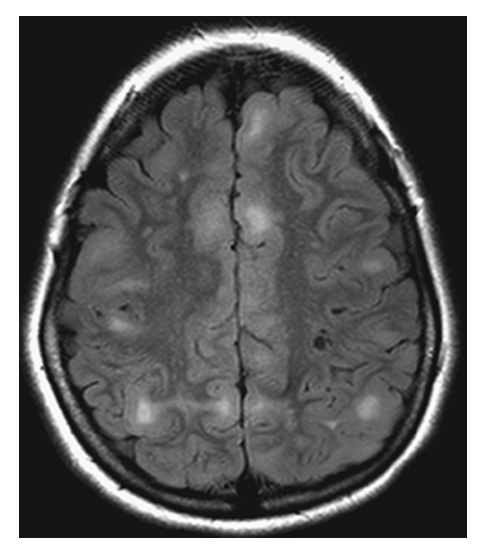

What is C

Glioblastoma Multiforme. shows high-signal edema.